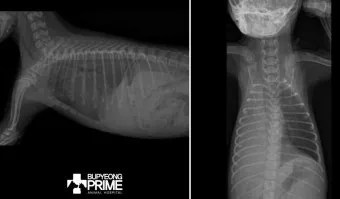

2단계, 흉부 X선 촬영입니다.

서서 찍은 단순 X선에서 보통 250mL 이상 흉수가 고이면 갈비뼈와 횡격막이 만나는 부분이 희미해지거나, 반달 모양의 음영이 보이기 시작한다고 알려져 있습니다.:contentReference[oaicite:21]{index=21}

3단계, 흉부 초음파·CT 검사입니다.

특히 초음파는 수십 mL 수준의 적은 양 흉수도 찾아내는 데 도움이 되고, 어디에 얼마나 모여 있는지를 파악해 나중에 흉강천자(물을 뽑는 시술)를 할 위치를 잡는 데 쓰입니다.:contentReference[oaicite:22]{index=22}